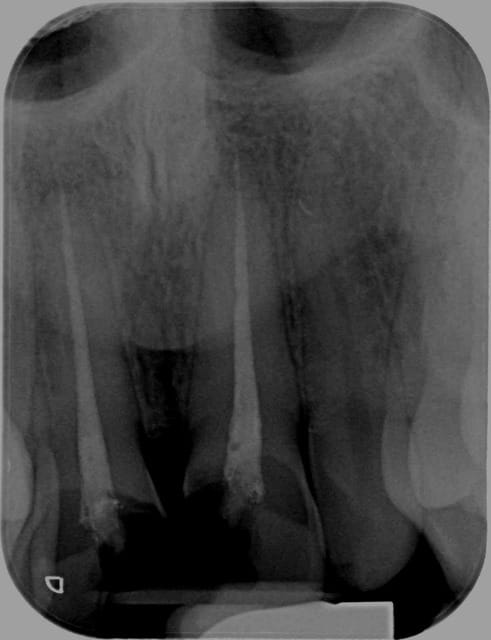

> je suis pas sûr que ce soit DANS le sinus... en vestibulaire?

Pas dans la bouche en tout cas.